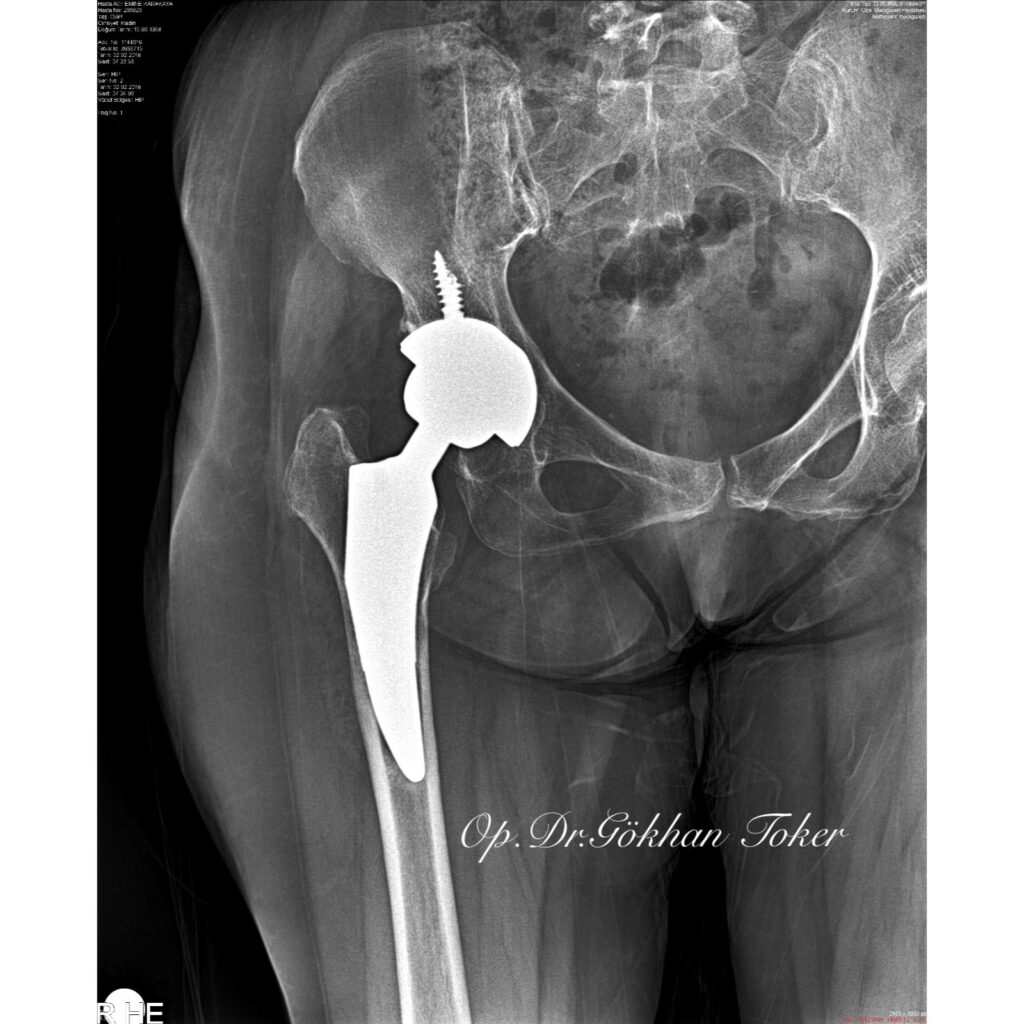

E.K.